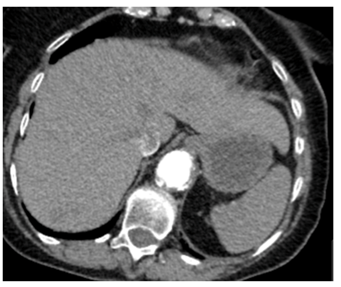

Three months later, she was presented to her general practitioner with vaginal bleeding and was evaluated in two weeks at the Gynecology clinic where on examination, a craggy 2-3cm mass, replacing the left Bartholin’s gland in the lower 1/3rd of vagina and vulva, was noted. This mass was biopsied which showed metastatic clear cell renal carcinoma. On a repeated contrast-enhanced staging CT chest, abdomen and pelvis, progression of her metastatic disease with an increase in the size of her left renal lesion to 7cm was observed (Figure 3&4). The patient was also noted to have become progressively thrombocytopenic. She was therefore, continued on the palliative care pathway with supportive treatment. At the time of submission of this article, patient was still alive under the care of the Oncologists who had discussed and commenced palliative Pazopanib at a reduced dose of 400mg daily. The patient’s main issue was bilateral lymphedema with not much symptoms from her vulvo-vaginal metastases.

Figure 3: Staging CT chest, abdomen and pelvis showing left renal lesion in December 2015.

Figure 4: Repeat stating CT chest, abdomen and pelvis showing progressive metastatic disease in August 2016.